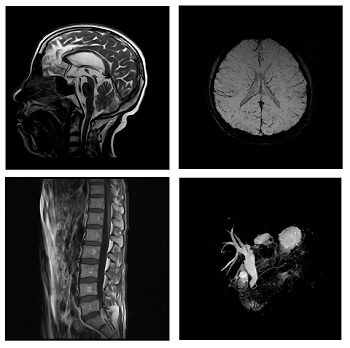

Marcom 1.5T es un escáner superconductivo de resonancia magnética de nueva generación con una intensidad de campo de 1,5 Tesla con capacidad para realizar exploraciones de todo el cuerpo, como: el sistema nervioso, la columna, los tejidos blandos de las articulaciones, la cavidad pélvica y abdominal, etc.

La mayor comodidad para el paciente con alta resolución y cortes finos mejora el diagnóstico y crea un resultado excelente.

Sistema de gradiente de alta eficiencia, bobina receptora de RF PA multicanal con identificación inteligente.